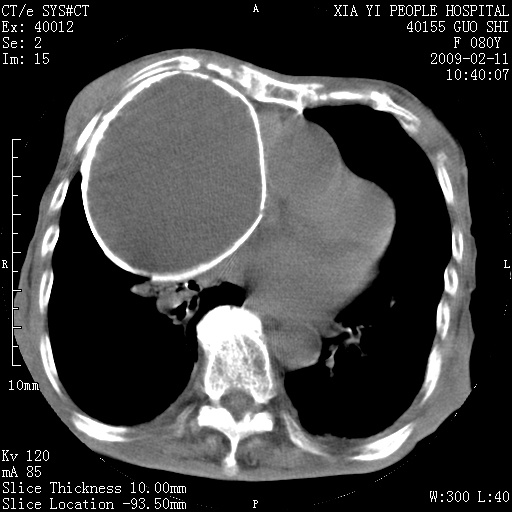

以下是引用随光逐影在2009-2-16 16:34:00的发言:[br]1)考虑右前纵隔皮样囊肿。2)双侧少量胸腔积液。

以下是引用zjzjr在2009-2-16 17:30:00的发言:[br]支持囊性畸胎瘤 双侧少量胸腔积液。